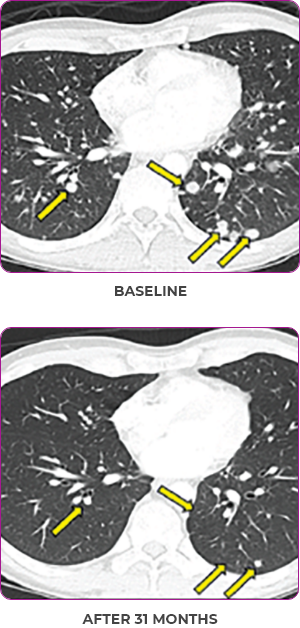

Response in primary and metastatic lesions1

Lung imaging of primary tumors.

SCAN 1: LUNG

SCAN 2: LUNG AND BONE

Response to VITRAKVI1

- Partial response and symptom improvement confirmed by chest X-rays after <1 month of treatment

- Imaging performed 6 weeks into treatment revealed considerable decrease in the size of both target lesions

- No treatment-related AEsa were reported

- Complete clinical response achieved by 12 months with residual scarring

- Patient was symptom free and remained on VITRAKVI